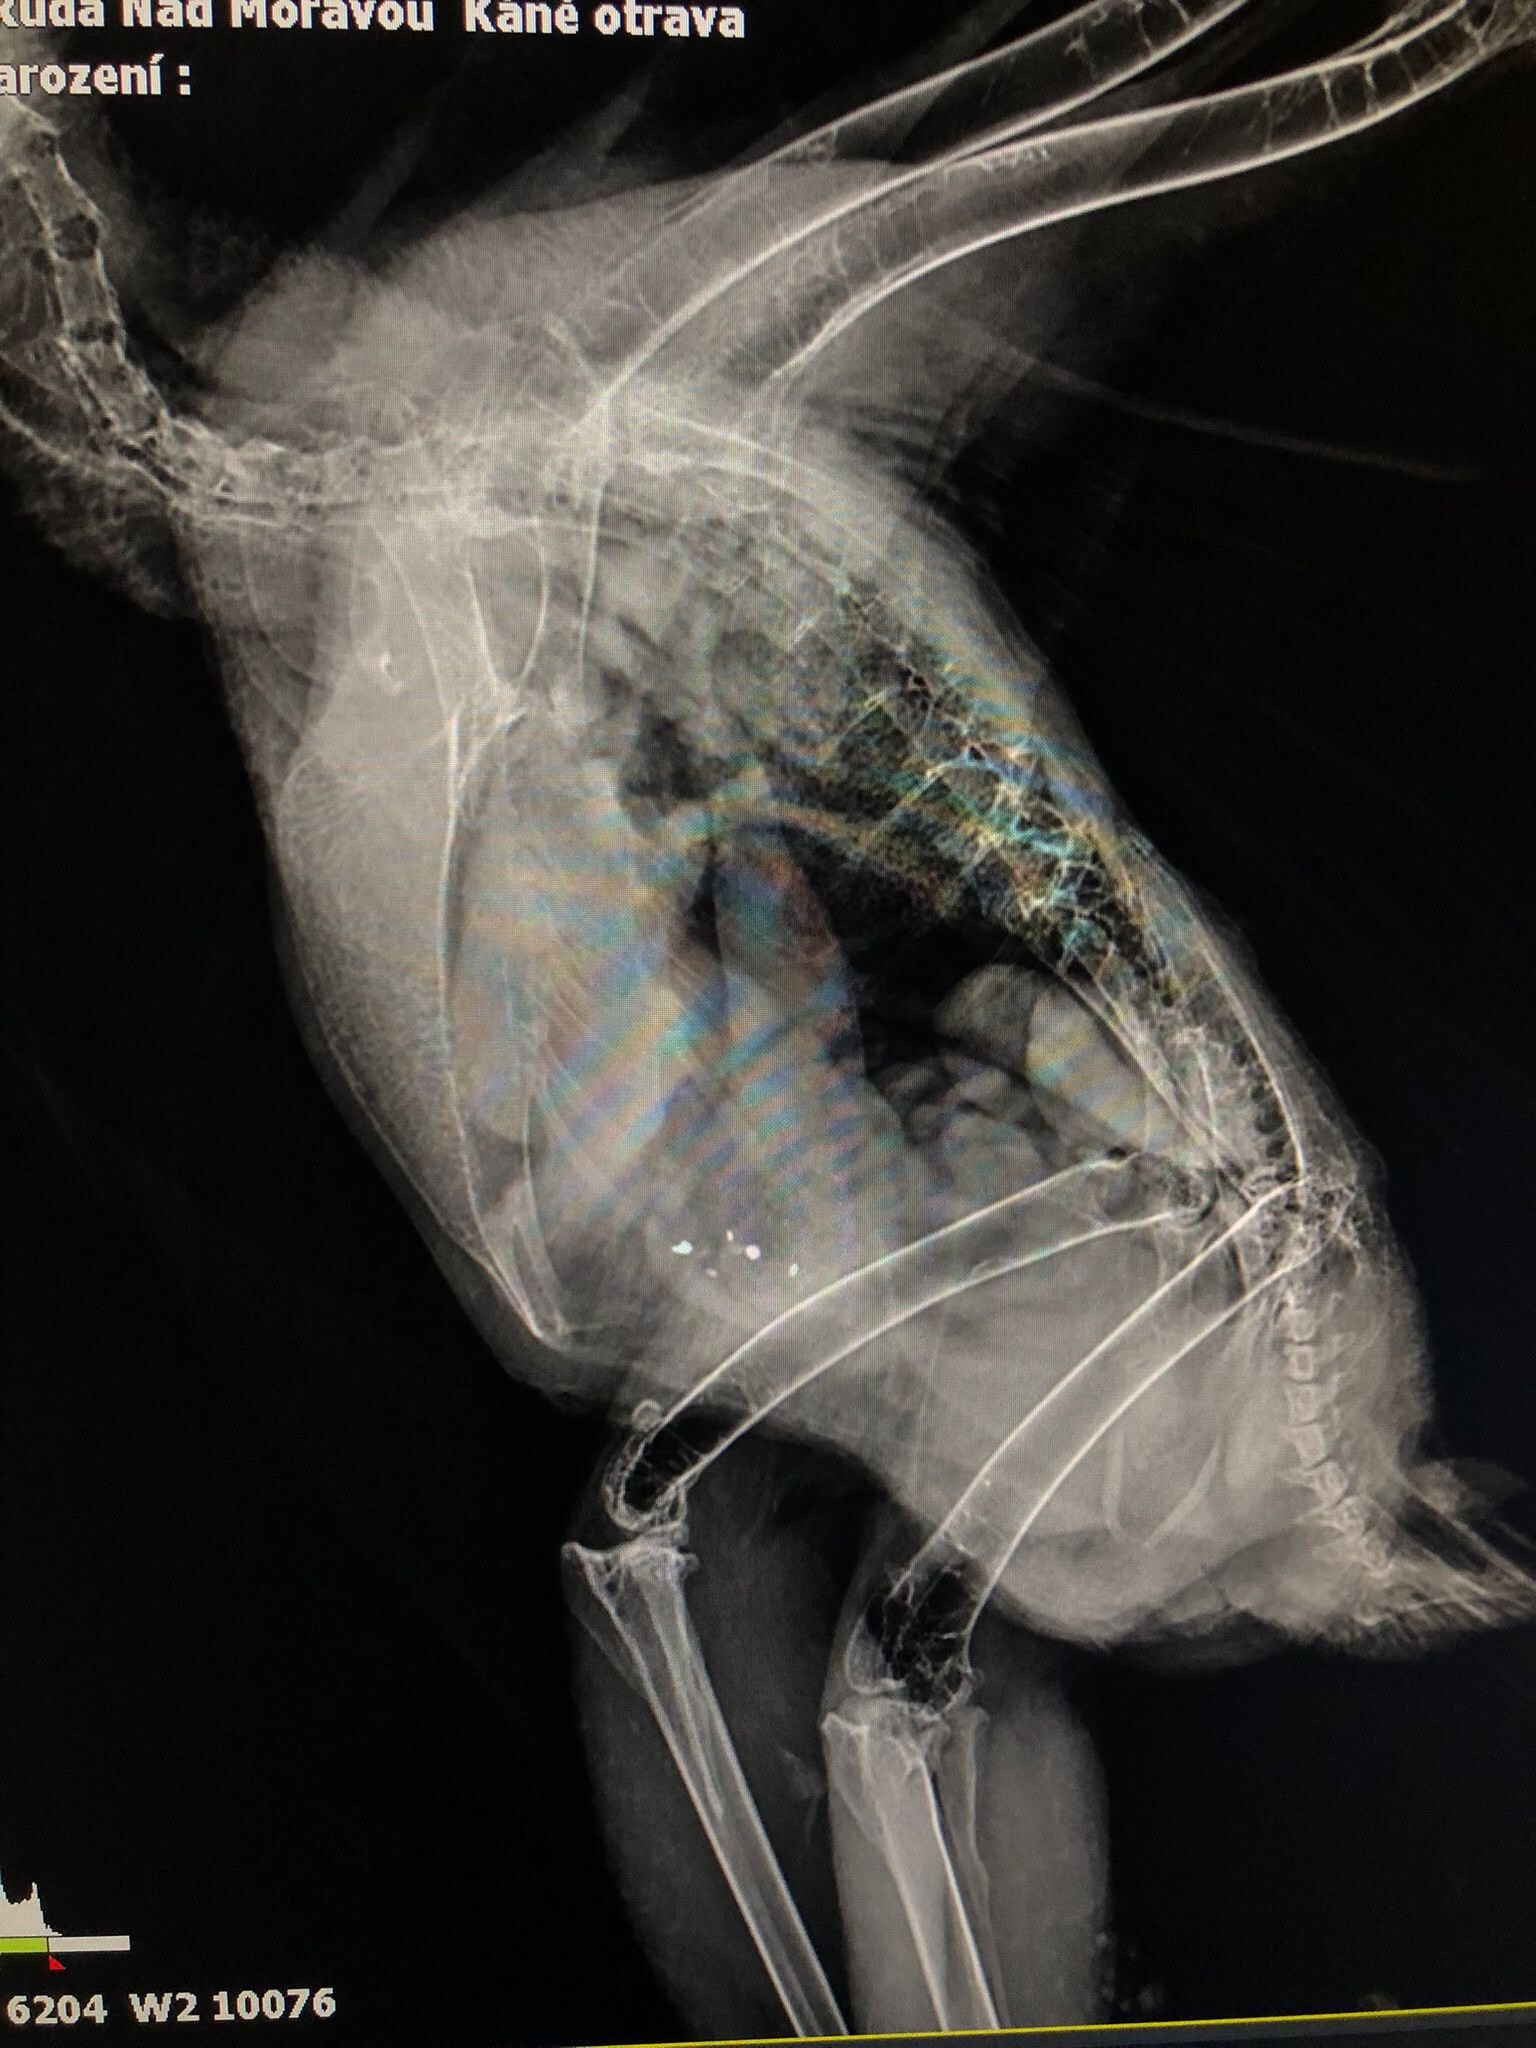

zdroj: Facebook Záchranná stanice Ruda nad Moravou